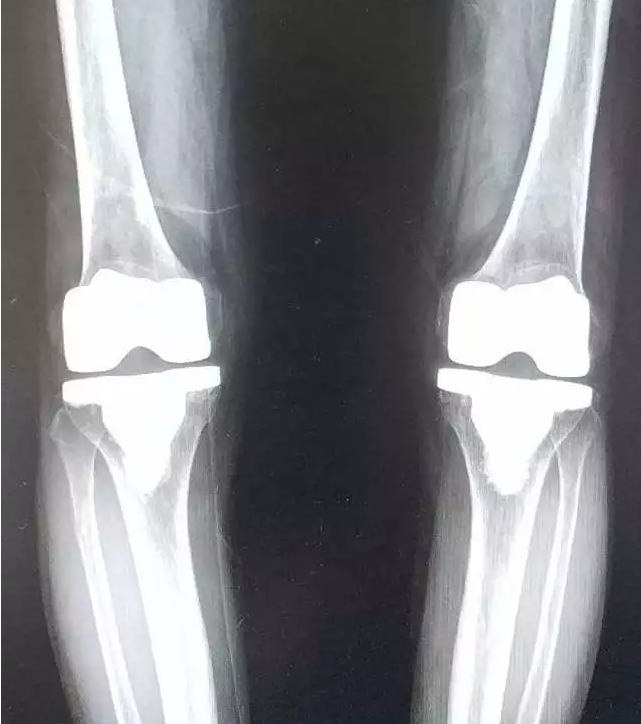

▲

李奶奶术前双膝X正位片,具有手术需求。

李奶奶术后双膝X正位片,已恢复关节功能。